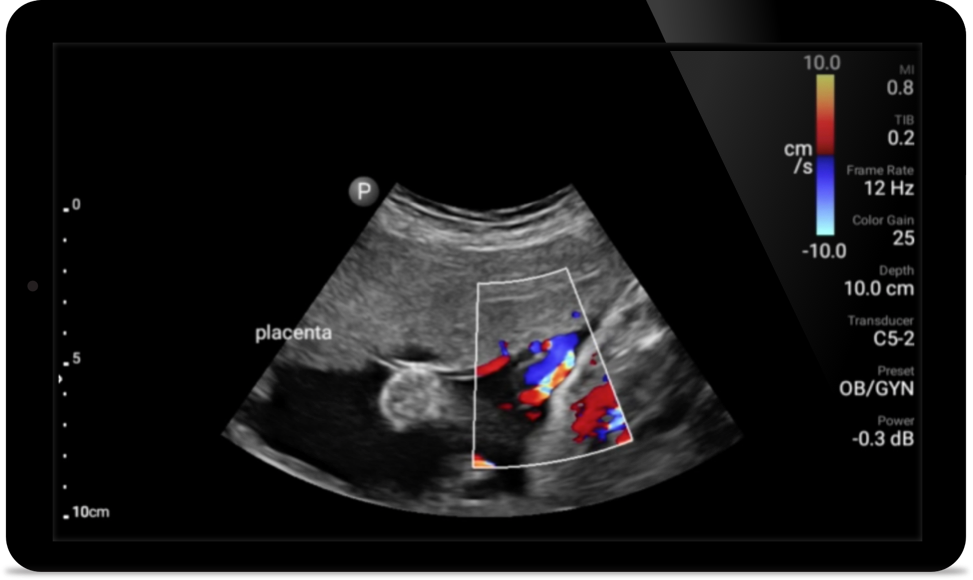

Opportunity to potentially reverse cardiomyopathy

Tutorial

Intro to transthoracic echocardiography